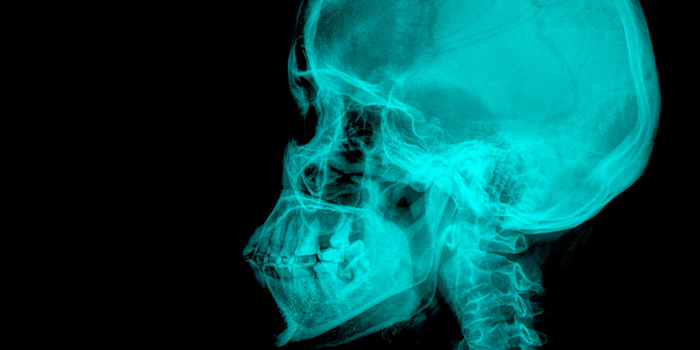

歯並びの悪化にも!? 顎偏位が全身に与える悪影響とは

顎偏位とは、下のあごが正常な位置からわずかに偏っている症状のこと。

上あごとのバランスが崩れて、左右に歪んでいる状態です。

そのため、ズレが大きい人ほど顔のパーツや輪郭が左右均等ではなくなります。

さらには顔だけでなく、全身に悪影響が出る恐れもあります。

体全体のバランスが悪くなり、さまざまな症状に繋がってしまうのです。